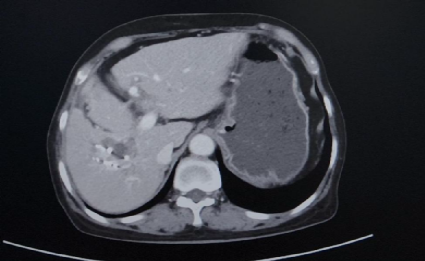

CT(2025.2.18):1、肝右叶异常强化团块影伴周围胆管扩张,考虑肝内胆管癌可能性大,门静脉右支充盈缺损影,考虑癌栓形成。2、脾脏缺如;胆囊、胰腺、双肾及双侧肾上腺未见明显异常

TACE术后28天影像学检查

与2025-02-18日腹部增强片对比示:1.肝右叶多发低密度结节,考虑胆管癌,最大病变内多发颗粒状致密影,考虑介入术后改变,较前病变内坏死增多。肝中静脉局部走行于病灶边缘,管腔未见明显受侵。2.门脉右支起始处少许癌栓,远端未见显影,考虑治疗后改变。3.脾脏缺如;胆囊继发性改变,胆囊窝积液。肠系膜间可见多发稍大淋巴结。